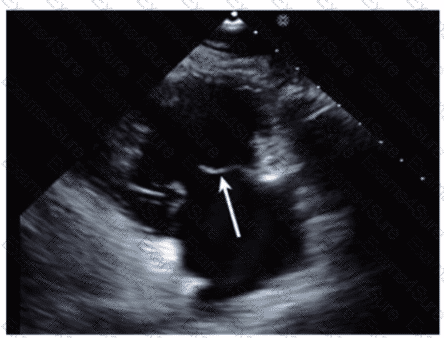

Which phase of the cardiac cycle is indicated by the arrow on this image?